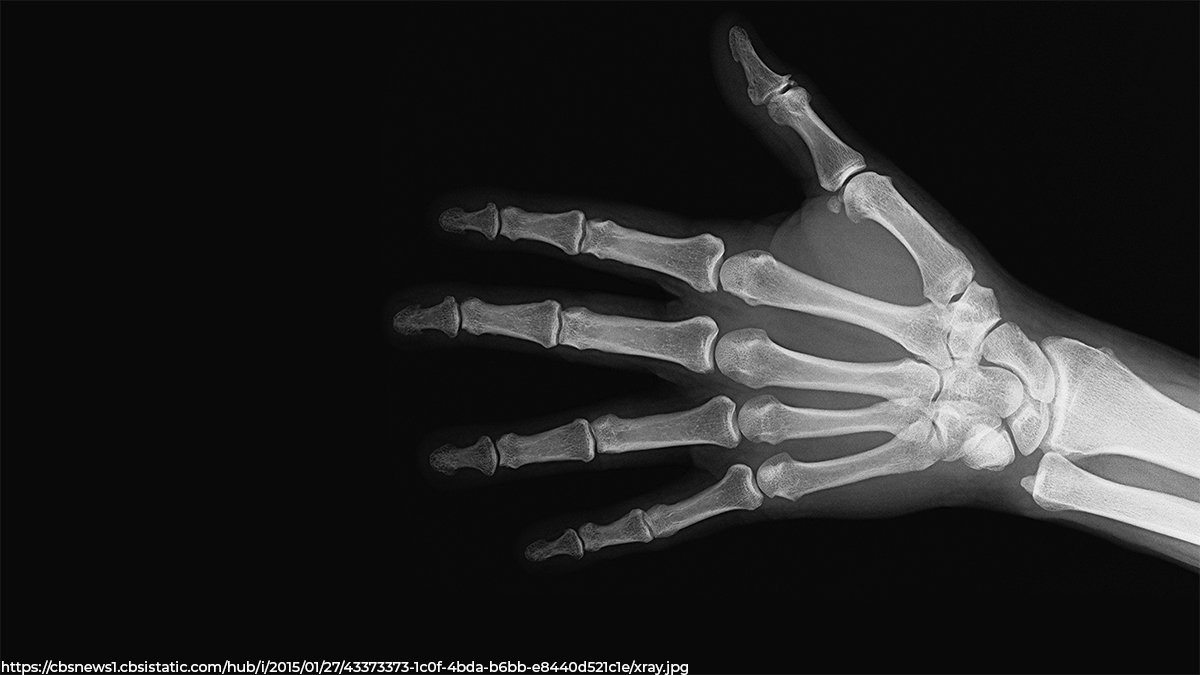

С сотрудницей предприятия города Владимира произошел несчастный случай на производстве - женщина получила травму ножом для резки пленки, ударившим в область сочленения кисти и предплечья правой руки. Кисть пострадавшей практически была оторвана от предплечья и держалась только на малом кожном лоскуте по тыльной поверхности. Сосуды, нервы, сухожилия и основная часть мягких тканей была отсечена, рассказывает минздрав Владимирской области.

Фото пресс-службы минздрава Владимирской области